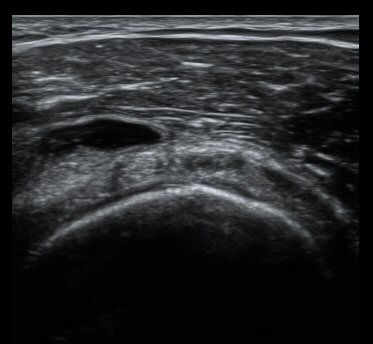

ȸÀü±Ù°³°£°Ý Ⱦ´Ü¸é°Ë»ç¿¡¼­ Á¡¾×³¶³» ¼ö¾×Àú·ù°¡ °üÂûµÈ´Ù(±×¸² 1). ÀÌµÎ¹Ú±Ù°Ç °í¶û¿¡¼­´Â ƯÀÌ ¼Ò°ßÀ» º¸ÀÌÁö ¾Ê´Â´Ù(±×¸² 2). ȸÀü±Ù°³°£°Ý ³»Ãø¿¡¼­ °ß°©ÇϱٰÇÀÇ ÆÄ¿­°ú Á¡¾×³¶³» ¼ö¾×Àú·ù°¡ °üÂûµÈ´Ù(±×¸² 3, 4). ±Ø»ó°Ç Ⱦ´Ü